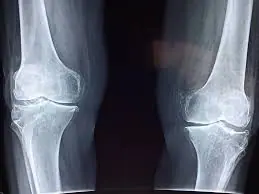

🦴 Fragilité osseuse : un danger méconnu

Peu de gens le savent, mais les sodas peuvent affecter la solidité des os. Pourquoi ? Parce qu’ils remplacent souvent les boissons riches en calcium comme le lait ou les boissons végétales enrichies. Chez les jeunes, cela peut nuire à la construction du capital osseux ; chez les adultes, cela fragilise les os sur le long terme.